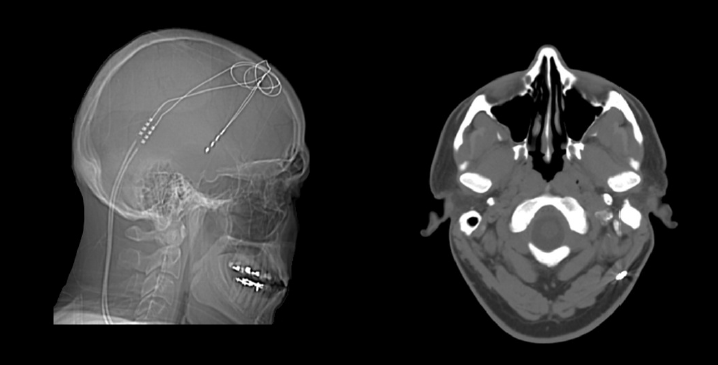

Over the past three years, the team successfully treated the man with an experimental form of electrical brain stimulation, called deep-brain stimulation (DBS). To date, DBS has been used most frequently to lessen symptoms in people with advanced Parkinson’s disease and also on an experimental basis to help lift otherwise untreatable, severe depression. Worldwide, only around 100 other people with OCD have been reported to have received DBS treatment on a trial basis. This was the first such instance, however, in which an individual with such severe mental illness, being treated with DBS, also consented to and received whole-genome sequencing, and rigorous post-sequencing analysis of the results, accompanied by genetic counseling.

Each phase of the study generated significant data; but never had such data been integrated in the context of a single clinical psychiatric case. The results, which appear online today in the journal PeerJ, show that the patient was greatly helped by DBS. Over the treatment period, symptoms associated with OCD diminished to the point that the individual was able to “regain a quality of life that he had not previously experienced in over 15 years,” Dr. Lyon and colleagues report. As the electrical stimulation of his brain via DBS was optimized over time (this involved gradually increasing the voltage used in electrical stimulation), he was able to participate in regular exercise, work as a volunteer, and eventually meet someone and get married.

The researchers noted that several times during the treatment, when power from the battery that drives the DBS signals was either drained or not activated by the patient, symptoms of severe OCD returned over the course of 12-24 hours and rapidly became debilitating. This was both a powerful lesson to the patient to keep the device charged (the battery is rechargeable) and vivid evidence to the scientists regarding the device’s role in producing the patient’s observed symptomatic improvements.